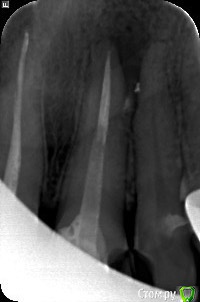

Прикладываю снимок после резекции, сегодня была на консультации у другого специалиста, сказал, что мало прошло времени для беспокойства. Но он не работал с биос материалом и опыта по проведению резекций у него мало.

post-31623-0-71940100-1445705182_thumb.jpeg

Сделайте прицельный снимок или новую КТ, выкладывайте и будем смотреть

Уважаемый Гарриевич :-) (извините, не знаю как к Вам обратиться), не могли бы вы посмотреть снимок? В ближайшее время я буду встречаться с доктором, проводившим резекцию, хотелось бы до встречи понять как обстоит дело (все плохо или жить буду :-)) и какой тактики, по вашему мнению, дальше придерживаться. Заранее спасибо и если, что извините за назойливость. Изменено пользователем Vilka

Тактику стоило выбрать изначально другую, но даже в вашем случае не смертельно. Время прошло действительно мало, возможно правильным решением будут регулярные осмотры у доктора, в динамике будет видно. На счёт ощущения крошек и прочего подсказать сложно.